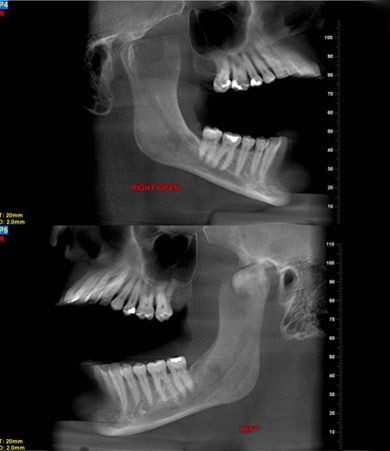

A sagittal series of tomograms (Figure 3) demonstrated a variable opacity with well-formed margins in the left condyle. There was a small ovoid lucency extending through the structure. The head of the mass appeared to extend anteriorly well beyond the fossa.

Figure 3